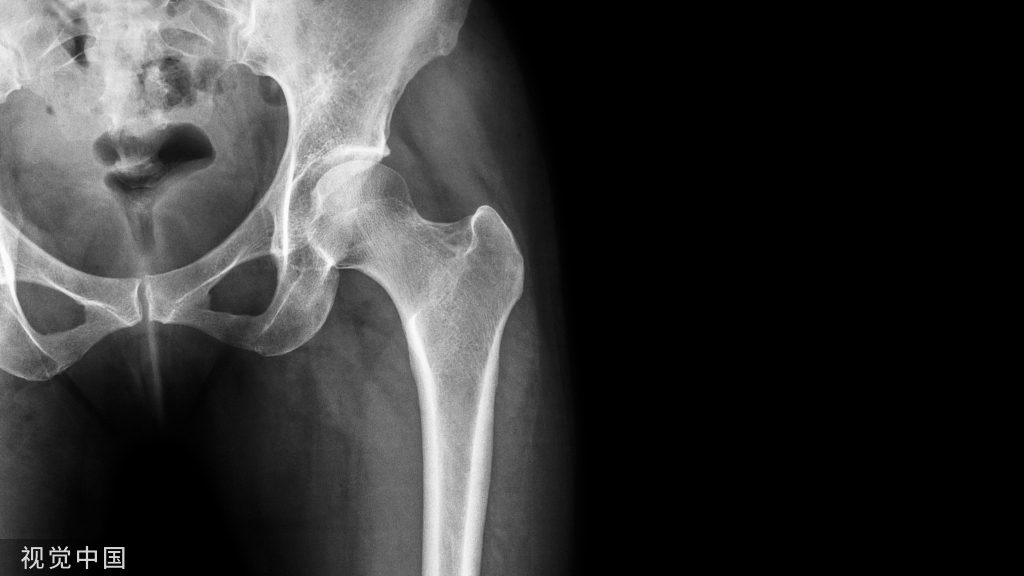

髌骨是人体最大的籽骨。它是股四头肌和髌腱之间伸肌机制的支点。髌骨将股四头肌的力臂向前移动,从而提高伸展力的效率。髌骨骨折最常发生在老年人单纯跌倒后,开放性骨折罕见。对于老年患者,骨折也可能发生在全膝关节置换术周围,或者可能是由于病理损伤造成的。

老年患者治疗的首要目标是恢复功能。治疗以骨质量、骨折模式、体检以及患者的功能状态和医疗合并症为指导。治疗选择包括非手术治疗、切开复位内固定、部分髌骨切除术以及极少数情况下的全髌骨切除术。